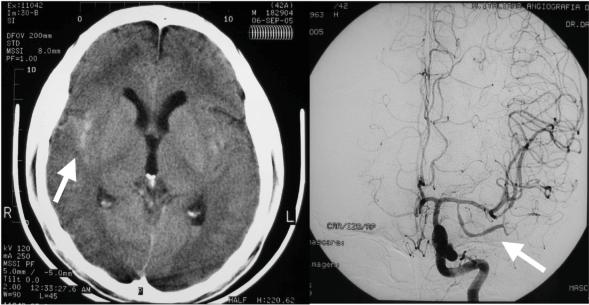

Meningitis due to non-typhi salmonella is infrequent in HIV-positive adults.We report a case of a patient with >300 CD4+ cells/mm3 who presented with five episodes of recurrent meningitis, focal subarachnoid hemorrhage and cerebral vasculitis ultimately attributed to Salmonella choleraesuis infection. Even within the cART era invasive salmonellosis can occur in unusual ways in HIV-infected patients.

非伤寒沙门氏菌引起的脑膜炎在HIV阳性成年人中并不常见。我们报告了一例CD4+细胞计数>300个/mm³的患者,该患者出现了五次复发性脑膜炎、局灶性蛛网膜下腔出血和脑血管炎,最终归因于猪霍乱沙门氏菌感染。即使在抗逆转录病毒治疗(cART)时代,侵袭性沙门氏菌病在HIV感染患者中仍可能以不寻常的方式发生。